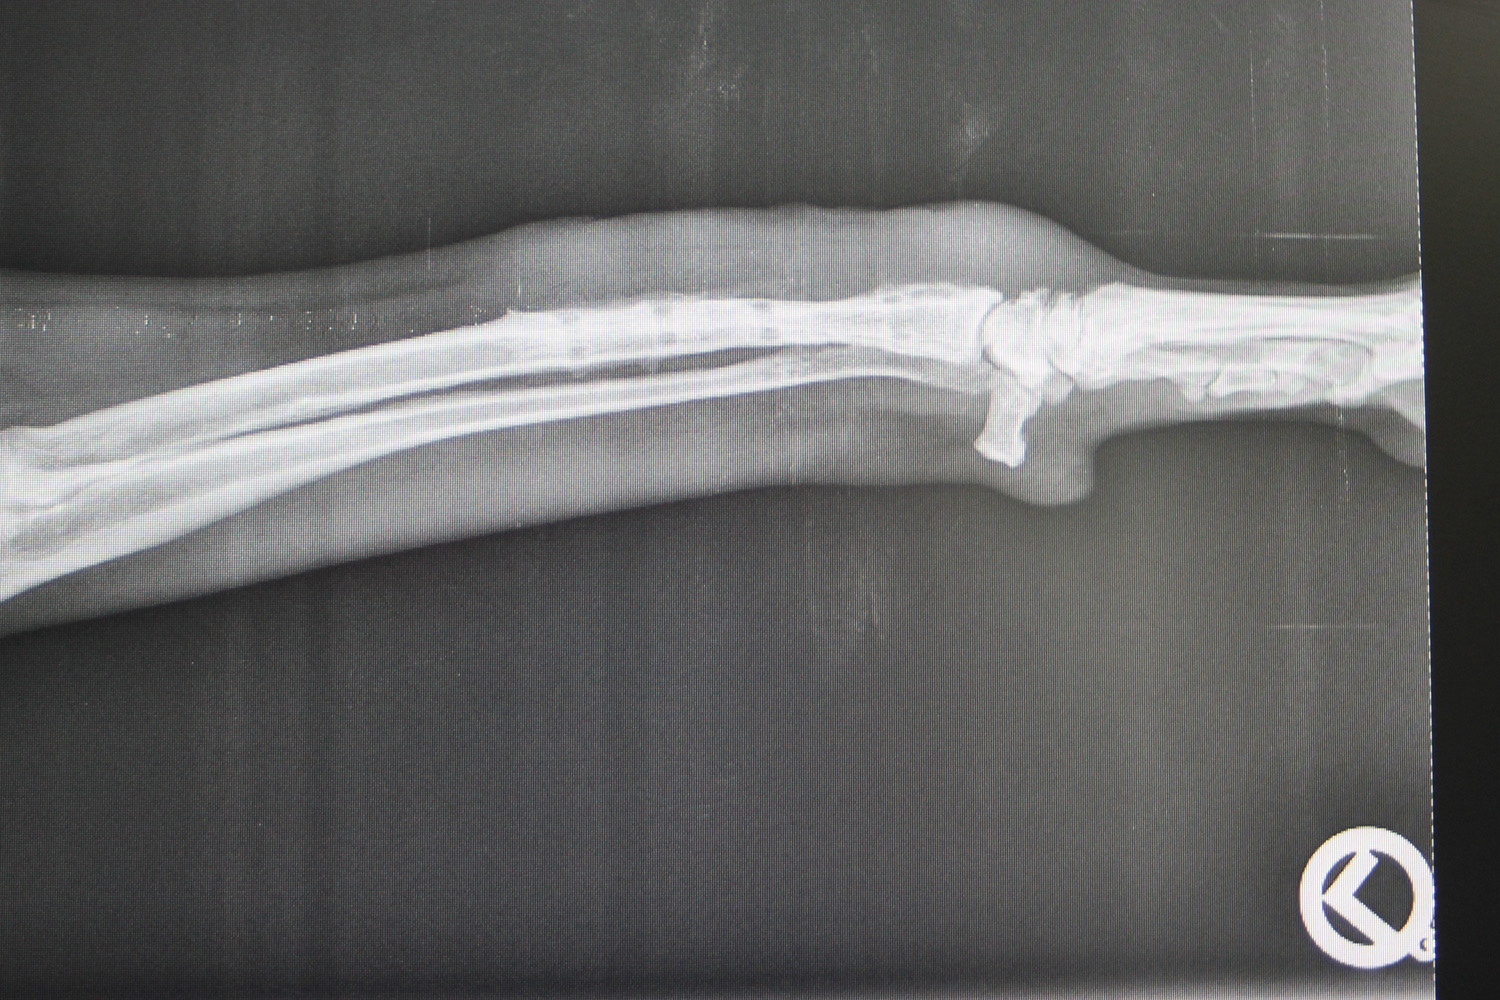

Röntgen, Ultraschall und auch die Endoskopie gehören bei uns zu den bildgebenden Diagnosemethoden, die routinemäßig angewendet werden. Viele Erkrankungen lassen sich erst durch diese weiterführenden Untersuchungen zweifelsfrei feststellen.